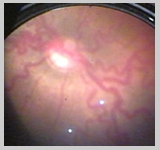

| AP-ROP (Aggressive

Posterior ROP):

Corresponde a un subgrupo de ROP de aparición precoz y curso

agresivo y acelerado. Hoy la denominamos Agressive Posterior ROP

(AP-ROP) (50), antes llamada enfermedad RUSH.

Suele ser una ROP posterior y presentarse con morfología

atípica, tiende a desarrollarse en 360 grados y se acompaña

de Plus en los cuatro cuadrantes y de hemorragias retinales. Requiere

tratamiento más agresivo y más precozmente, alrededor

de las 4-5 semanas de vida. Hemos realizado tratamiento a pacientes

con AP- ROP tan precozmente como a las 31,5 y 32 semanas de edad

postmenstrual.

En estos pacientes la dilatación venosa y tortuosidad

vascular o enfermedad Plus suele ser mucho más acentuada.

En ocasiones observamos verdaderos loops arteriovenosos que suelen

regresar una vez que la enfermedad ha sido tratada.

Las hemorragias retinales se ubican no sólo a nivel del

ridge o en el límite entre la retina vascular y avascular,

sino en todo el plano de la retina vascular. Aparecen como verdaderas

petequias sobre esta.

Observamos además gran ingurgitación de la túnica

vasculosa lentis y dificultad en la dilatación pupilar. En

estos pacientes la dilatación pupilar suele ser más

difícil pero siempre se logra y es fundamental la combinación

de fenilefrina y tropicamida.